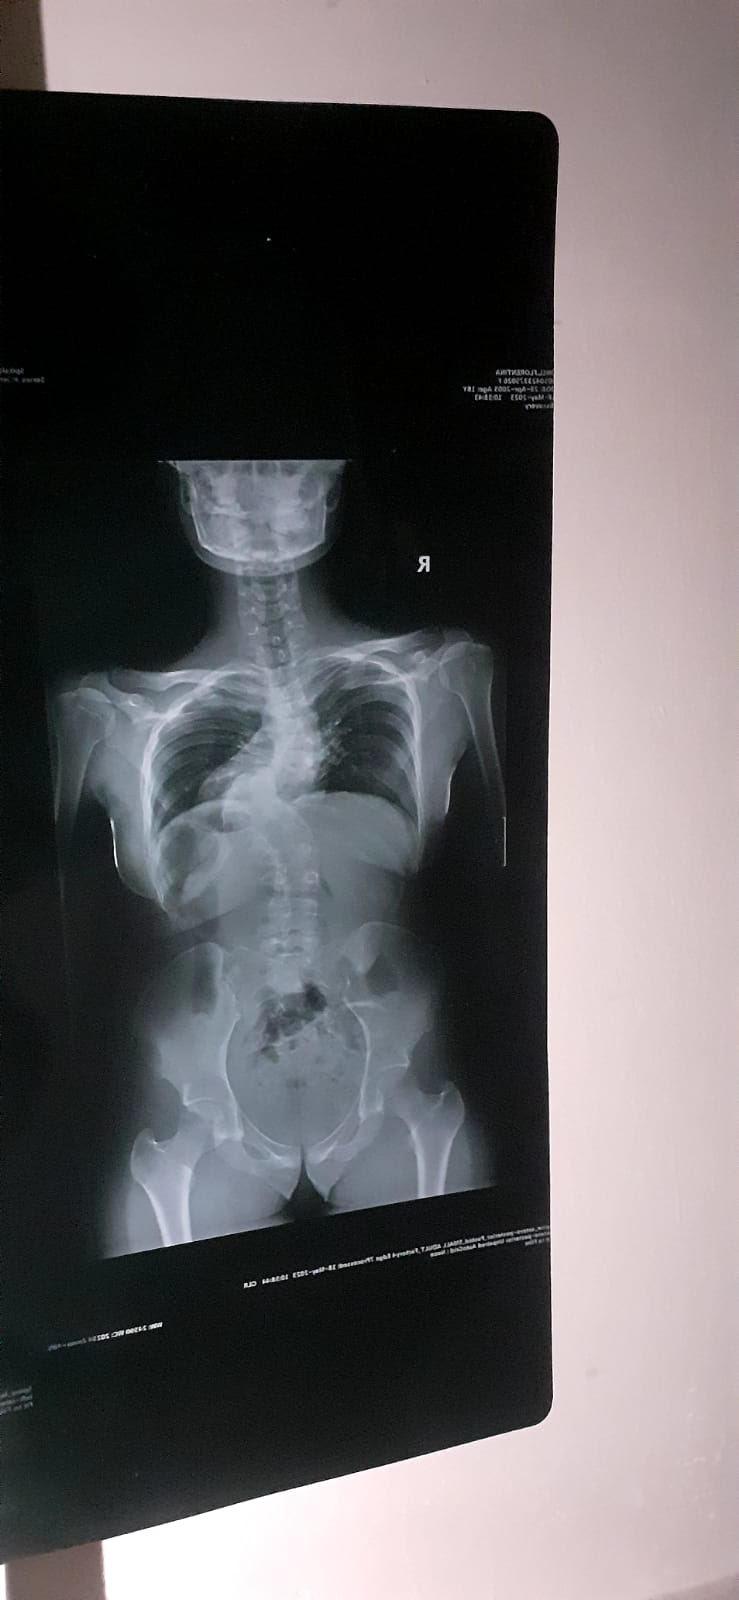

Din păcate, la o vârstă fragedă a fost diagnosticată cu scolioză, o afecțiune care i-a afectat coloana vertebrală și i-a transformat viața într-o luptă constantă cu limitările fizice.

Tânăra a fost diagnosticată cu scolioză la vârsta de 4 ani, lucru care i-a afectat semnificativ viața. Fata nu poate merge pe jos la școală, nu poate sta prea mult în bancă în aceași poziție și depinde complet de părinți pentru orice activitate care implică efort fizic.

Am purtat corset o perioadă, dar durerile de spate nu încetau, ba chiar s-au intensificat pe măsură ce creșteam. Nu pot sta mult timp în aceeași poziție și uneori nu pot respira normal din cauza presiunii asupra plămânilor.”, a explicat Florentina.